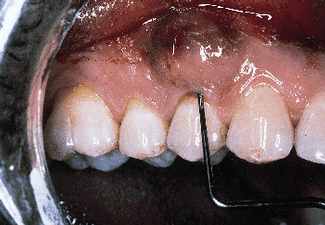

A nonresorbable membrane for GTR was placed over the defect as seen in Photograph #4. The membrane was composed of e-PTFE and was obtained from the W.L. Gore Co. in Flagstaff, Ariz.

Photograph #4: An expanded polytetrafluorethlyne membrane was placed over the root surface and secured. The facial flap was then sutured over the membrane.